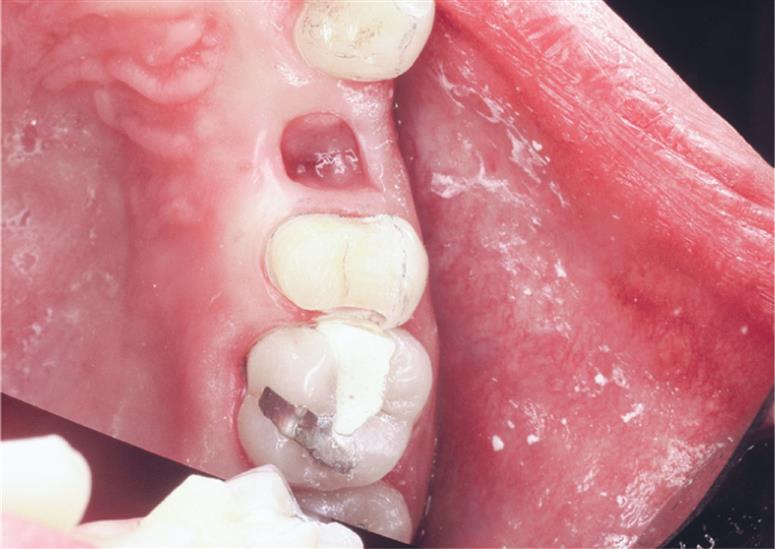

The step-by-step preparation of a three-quarter crown is illustrated on a maxillary premolar (Fig. 11.4). Except for a narrow bevel or chamfer margin placed along the bucco-occlusal line angle, the buccal surface of the abutment remains intact. The other surfaces (including the occlusal surface) are prepared to accommodate a casting in the same manner as a complete crown preparation (see Chapter 8), differing only in the need for proximal axial grooves to develop resistance form.

Upon the completion of occlusal reduction, the clearance on the functional cusp should be at least 1.5 mm, and those on the nonfunctional cusp and in the central groove should be at least 1.0 mm. Simultaneously, the tooth should be prepared so that metal display is minimal; the original outline form of the buccal wall should be preserved as well as possible.

Depending on available access, it may be feasible to complete the flaring with the same rotary instrument that was used to place the groove (Fig. 11.13). However, removing the last “lip” of unsupported tooth structure with a chisel is often a better option because this minimizes the risk of damage to the adjacent tooth.